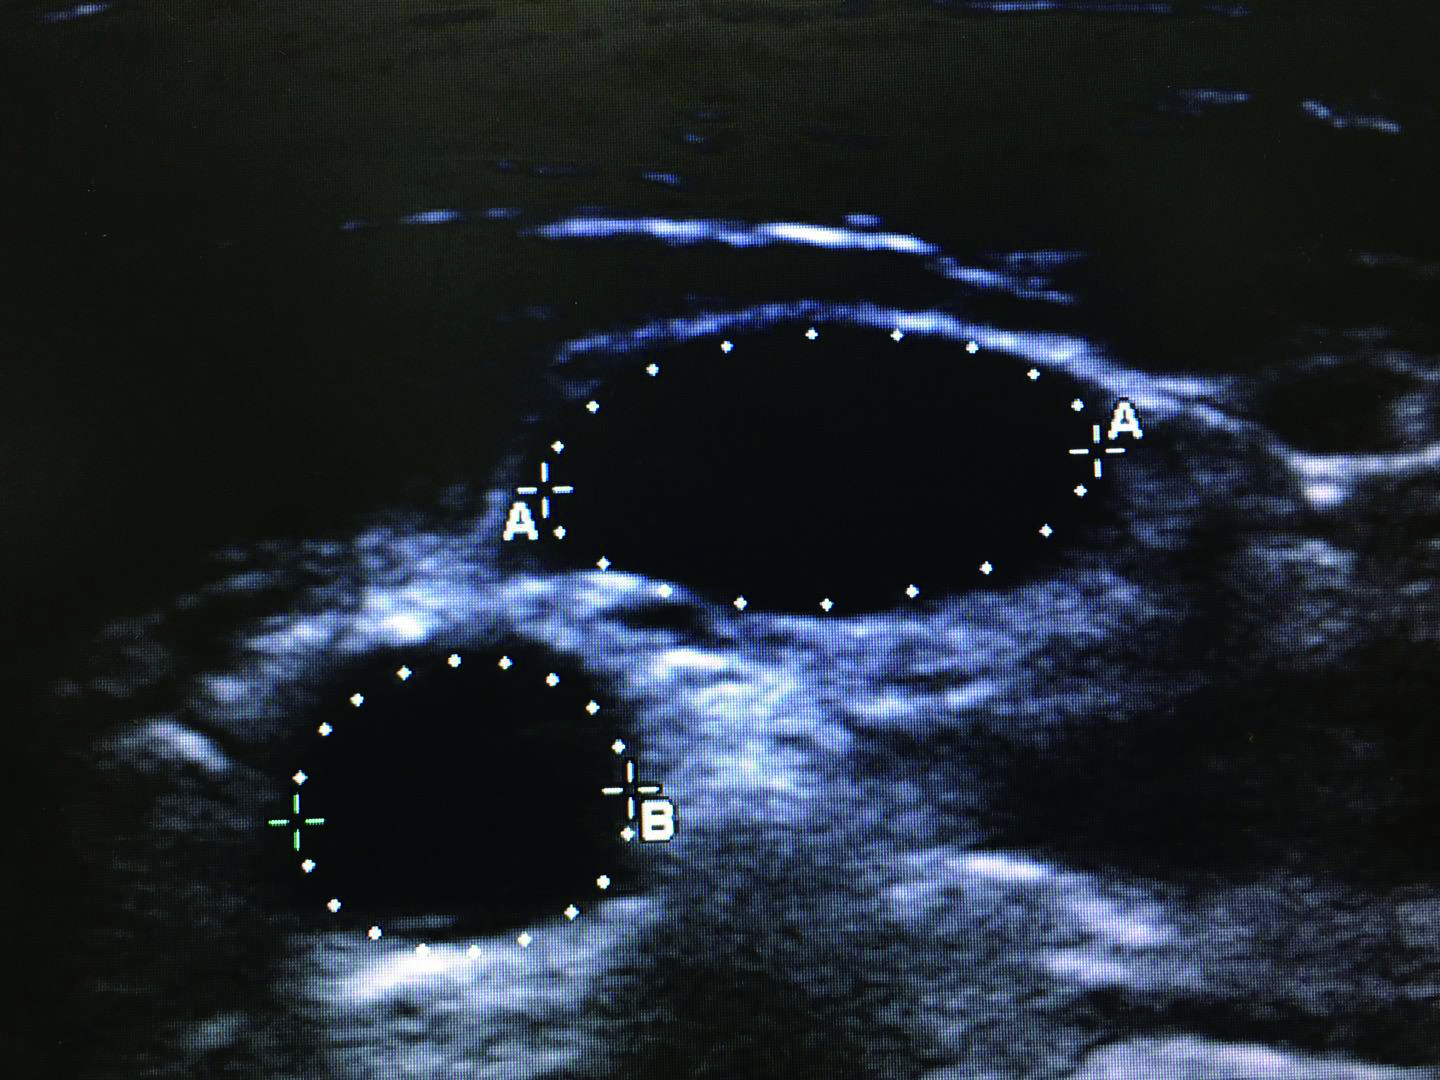

1.2.1 IJV/CCA截面积比值测量及计算方法患者取去枕平卧位,充分暴露颈部,选择甲状软骨最低位,将超声探头轻放于颈部血管处,分别测得头部正位时,双侧颈内静脉与颈总动脉横截面,冻结超声图像,使用电子标记界定颈内静脉和颈总动脉横截面的长径,同时,使用电子标记测得横截面周长,并且使用预先加载到超声单元中的程序计算颈部血管的横截面积,最后计算IJV/CCA截面积比值(图 1)。

| 图 1 超声电子标记的颈内静脉(A)和颈总动脉(B)周长 Figure 1 The perimeter of the internal jugular vein (A) and common carotid artery (B) electronic marked by ultrasound |